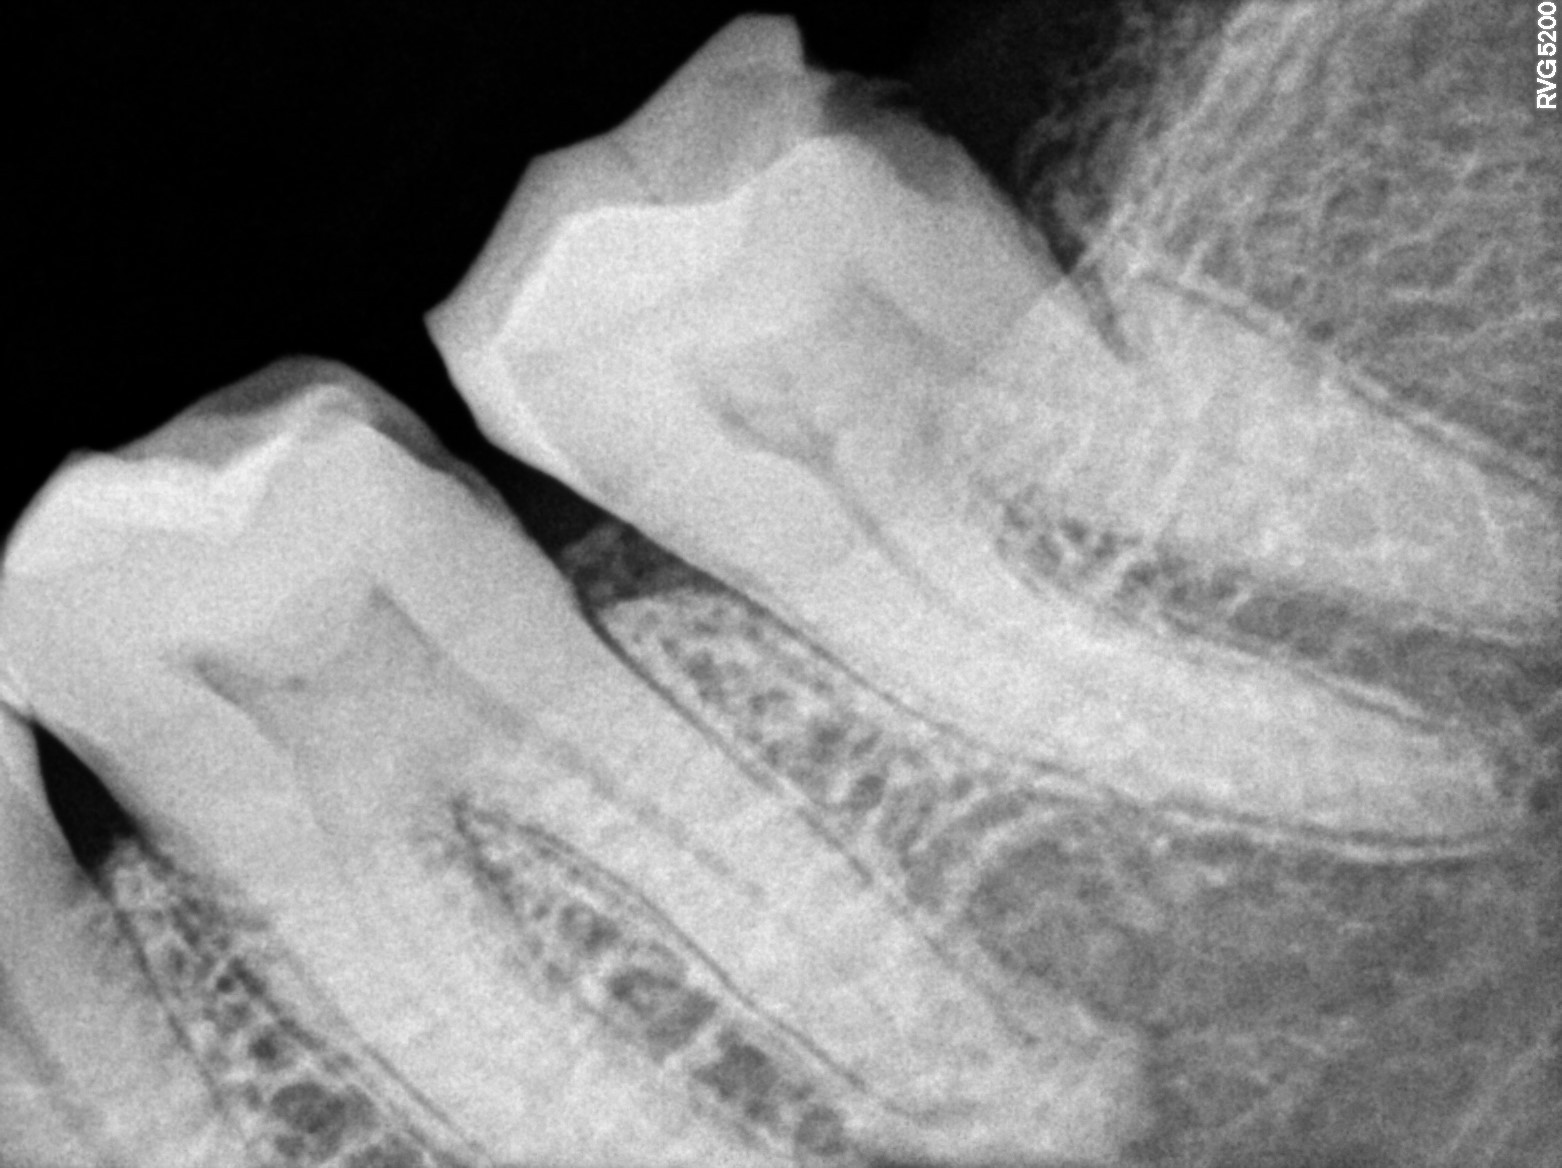

Dental Radiographs FHIR: DocumentReference · LOINC 24641-7

xray_1741706089.jpg

24641-7